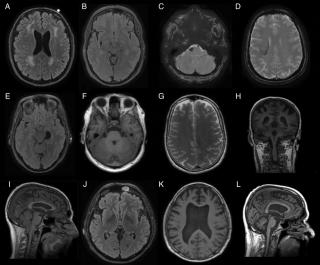

Магнитно-резонансная томография

МРТ позволяет четко визуализировать смещенную твердую мозговую оболочку, в виде гипоинтесивной линии на Т1 и Т2 последовательностях, что помогает отдифференцировть эпидуральную гематому от субдуральной.

Остая эпидуральная гематома имеет изоинтенсивный МР сигнал на Т1 ВИ и может иметь различную интенсивность МР сигнала на Т2 последовательностях.

Ранняя подострая эпидуральная гематома гипоинтенсивна на Т2 изображениях, в то время как поздняя и хроническая эпидуральная гематома будут иметь гиперинтесивный МР сигнал как на Т1 так и на Т2 последовательностях.

Внутривенное введение контраста позволяет визуализировать смещенные или окклюзированные венозные синусы в случаях венозного источника эпидурального гематомы.